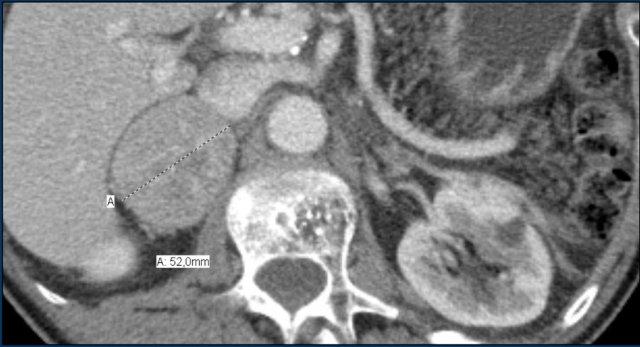

Các hình ảnh cho thấy u tình cờ tuyến thượng thận hai bên được phát hiện ở bệnh nhân 64 tuổi được chụp CT để phân tích phình động mạch chủ bụng.

Hình chụp pha động mạch cho thấy các tổn thương hai bên với tỷ trọng 50 HU.

Trên CT không tiêm thuốc thực hiện vài ngày sau, tỷ trọng ở cả hai tuyến thượng thận đều dưới 10 HU, xác nhận đây là các u tuyến giàu lipid.